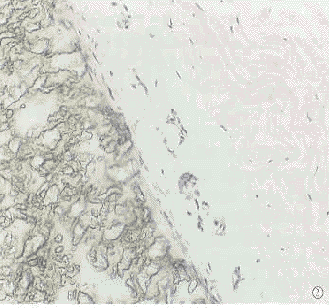

第2组第10天即可见到植入物纤维之间新生血管、纤维细胞分隔深入,炎性细胞少,可见异物巨细胞。随着时间延长,成纤维细胞及结缔组织伸入到植入片各纤维之间,第90天全部形成了植入片纤维与自身结缔组织互相交织的形态结构(图1)。

第3组植入片与巩膜之间以及植片结构间隙有较多的炎性细胞,随着时间延长,炎性细胞成分减少,植入片与巩膜之间可见潜在腔隙。植入物结构与巩膜的区别明显(图2)。

图1 术后第90天,植入的心包补片纤维与结缔组织相互交织(HE×20) 图2 术后第90天,血管补片与宿主巩膜仍不粘连,二者之间存在腔隙(HE×20) Fig.1 On d 90 after implanted surgically,the fibers of artificial pericardium are interwoven with connective tissue(HE×20) Fig.2 On d 90 after implanted sturgically,there was a gap between artificial vessel band and host scleral(HE×20)